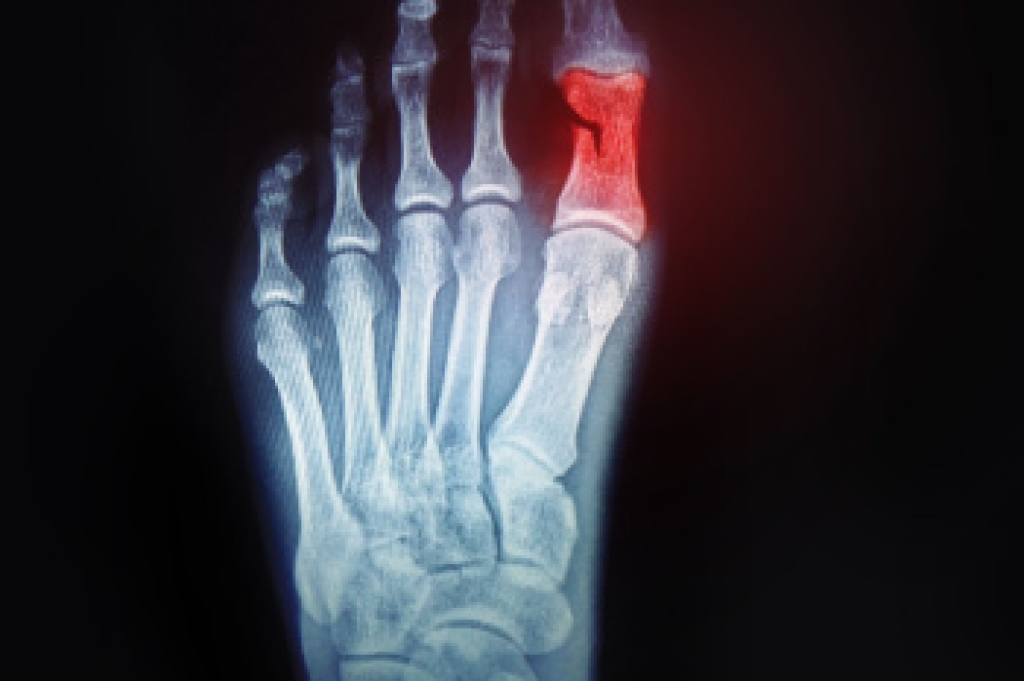

Morton's neuroma is a painful foot condition that commonly affects the areas between the second and third or third and fourth toe, although other areas of the foot are also susceptible. Morton’s neuroma is caused by an inflamed nerve in the foot that is being squeezed and aggravated by surrounding bones.